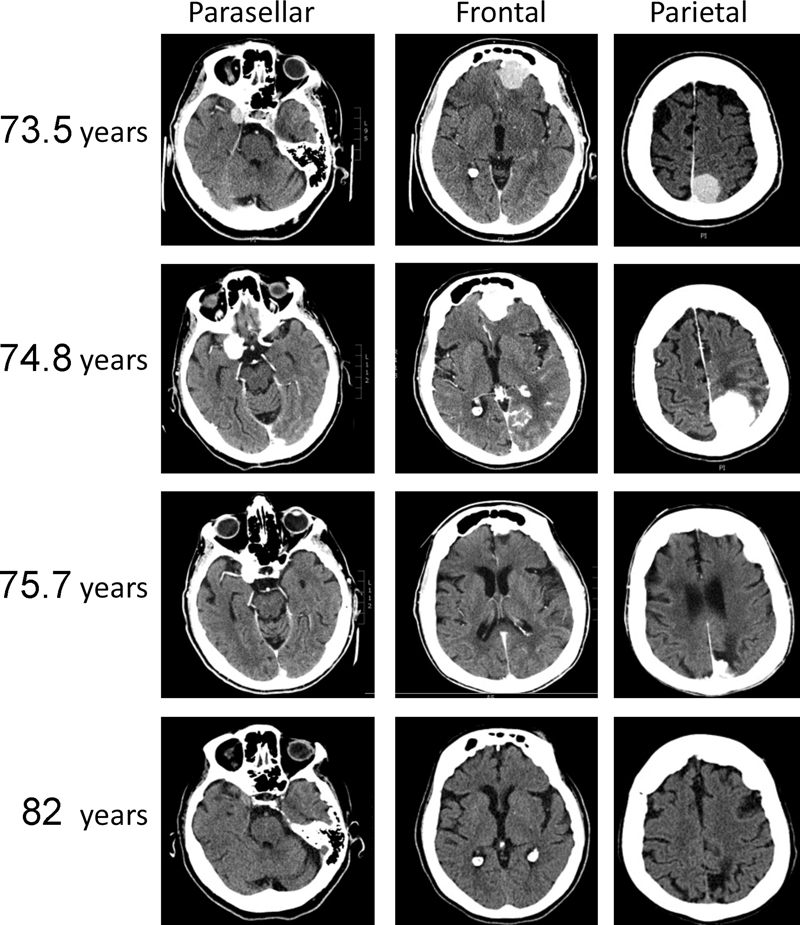

At age 73 years, the woman presented with labile emotions and confusion. She had a mild resting tremor but no localizing signs. A CT scan of the head showed three dura-based tumors in the left parietal / posterior falx region (2.9 cm), the left frontal / anterior falx region (2.8 cm), and the right parasellar region (1.7 cm) (Figures 1 and 2). Measurements presented in Figure 2 are from the CT scans. All tumors were isointense with gray matter on unenhanced imaging, and all were bright following contrast enhancement. The tumors were thought to be meningiomas. A single magnetic resonance (MR) study was incomplete because of claustrophobia. The brain tumors were isointense on the T1 sequence. Approximately 1 year later at 74.8 years of age, the woman stopped eating and was unable to walk, whereupon she was admitted to hospital. A CT scan at the time of admission showed further enlargement of two tumors with significant local mass effect and surrounding vasogenic edema (Figure 1). The woman was judged not to be a candidate for neurosurgical intervention. A CT scan two months after discontinuation of megestrol showed that the two largest tumors had decreased in size, whereas a new small en plaque tumor had appeared in the lateral part of the left frontal lobe. During a one year hospital stay without specific anti-neoplastic therapy, the neurologic status of the woman gradually improved. A CT scan at 75.7 years age showed that all tumors had decreased (Figure 1 and Figure 2). At age 76 years, the woman returned to independent living and regained her motor vehicle driving license.

At age 77 years her tremor had increased slightly. CT scans at 78 and 82 years age showed mild diffuse cerebral atrophy and all intracranial tumors had disappeared by 82 years age (Figure 1 and Figure 2). The woman died after choking on food at 83 years.

Figure 1. CT scans with contrast enhancement of brain showing dura-based tumors in the right parasellar, left frontal, and left parietal regions in a woman at ages 73.5 and 74.8 years when taking megestrol, and at ages 75.7 years and 82 years, after megestrol had been discontinued.